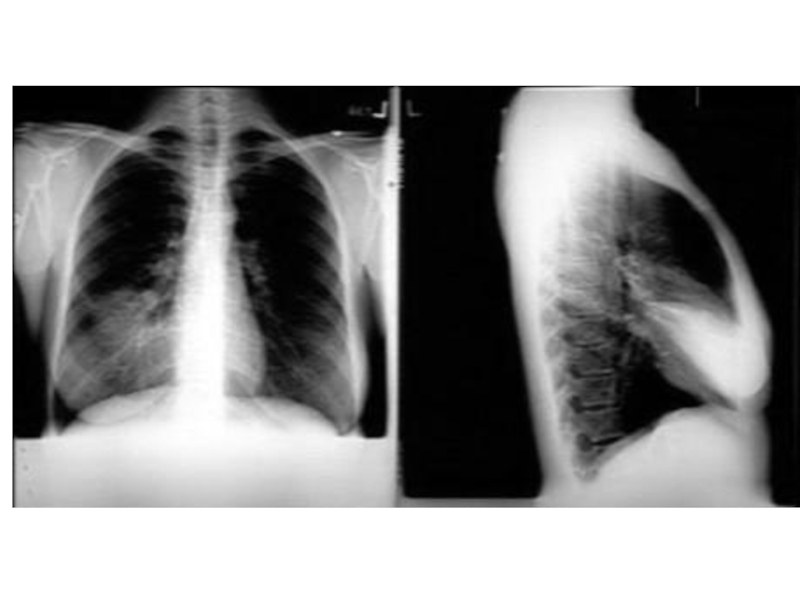

Рентгенологические признаки пневмонии – рентгенография является наиважнейшим и

незаменимым методом исследования для подтверждения клинического диагноза пневмонии.

При подозрении на пневмонию рентгенография грудной клетки выполняется в двух проекциях: прямой и боковой проекциях. Типичным рентгенологическим признаком пневмонии является затемнение легочной ткани, которое может быть очаговым, сливным, сегментарным (полисегментарным), долевым или еще более распространенным (тотальным). Изменения на рентгенограмме (распространенность инфильтрации, наличие или отсутствие плеврального выпота, полостей деструкции) указывают на тяжесть заболевания, помогают в выборе антибактериальной, симптоматической и другой (например, плевральная пункция) терапии.

Рентгенография органов грудной клетки. Рентгенологически характерным для крупозной пневмонии является гомогенное затемнение той или иной доли, или ее сегментов. При очаговой пневмонии у большинства больных выявляются очаговые тени средней или малой интенсивности, часто с неровными контурами.